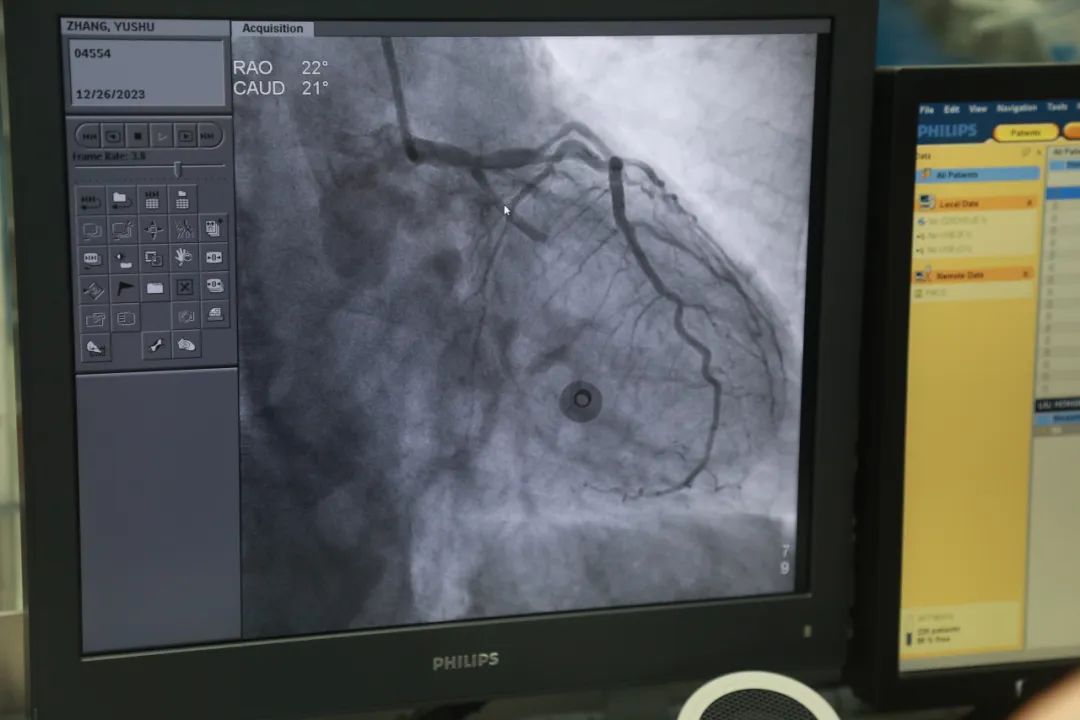

血压144/70mmHg,心电图:窦性心率,85次/分,初步诊断为:急性冠脉综合征、高血压病3级(极高危)。考虑到患者既往有骨折病史,右前臂血管畸形,CT胸部平扫提示:左肺上叶磨玻璃结节,右肺上叶实性结节。两肺肺大泡,动脉粥样硬化。

经紧急讨论并征求家属同意,心血管内科叶达平主任对患者实施冠状动脉造影术,对阻塞血管进行介入治疗并植入支架。

微创手术,伤口笔芯大小

术后:患者血管开通,胸痛症状迅速缓解。甚至看不到手术的疤痕,穿刺点大约圆珠笔笔芯大小。